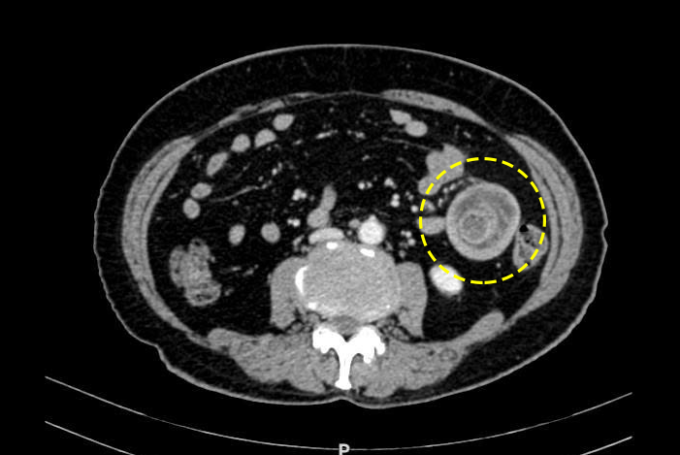

Bác sĩ có thể phát hiện lồng ruột khi khám lâm sàng. Siêu âm bụng có thể cho thấy lồng ruột nhưng độ nhạy kém hơn CT do bị ảnh hưởng bởi khí trong các quai ruột. CT cũng hỗ trợ xác định vị trí tắc nghẽn, đánh giá tình trạng mạch máu và định hướng xác định nguyên nhân gây lồng ruột.